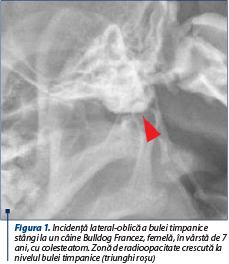

Examenul radiografic urmăreşte evaluarea conductului auditiv extern şi a bulelor timpanice, iar aspectele imagistice sunt în corelaţie cu evoluţia procesului patologic. Obişnuit, modificarea evoluează unilateral, însă au fost semnalate şi cazuri cu evoluţie bilaterală (Greci et al., 2011; Østevik et al., 2018). Modificările înregistrează aspecte diferite, în funcţie de momentul evolutiv al afecţiunii surprins pe imaginea radiografică. Se pot observa îngroşarea peretelui bulei timpanice, care prezintă un contur neregulat, precum şi dispariţia aerului din interiorul bulei, consecutivă dezvoltării timpanocheratomului, ceea ce determină creşterea radioopacităţii în interiorul bulei timpanice (figura 1).

Figura 1. Incidenţă lateral-oblică a bulei timpanice stângi la un câine Bulldog Francez, femelă, în vârstă de 7 ani, cu colesteatom. Zonă de radioopacitate crescută la nivelul bulei timpanice (triunghi roşu)